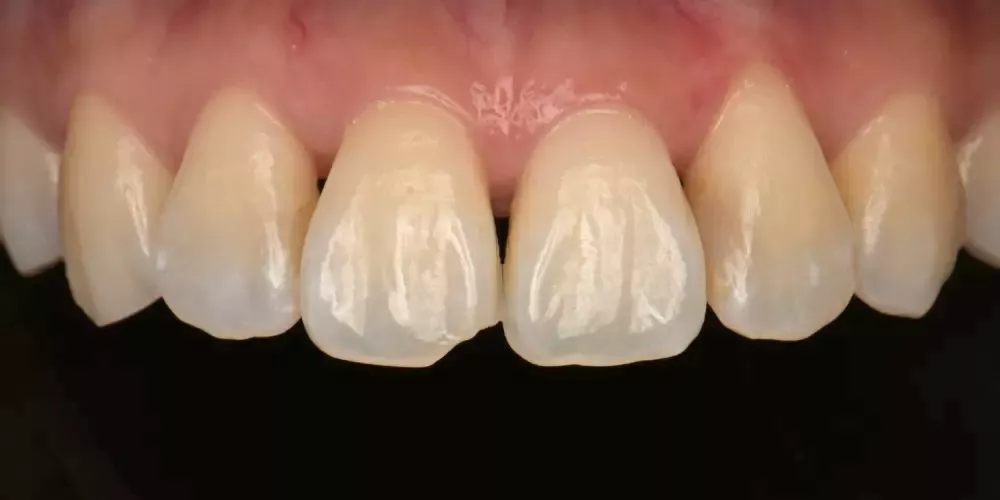

因此,每一次的治療,我都傾注最大的心力,在品質及細節上堅守高標準,讓成果真正經得起考驗。

一副笑容的改變,帶來的不只是外觀的提升,更深刻影響一個人在職場、人際與生活中的自信。相反的,一顆做得不夠好、撐不久的牙齒,或許短期內無痛無礙,卻會在無形中逐漸消磨一個人對生活的底氣。